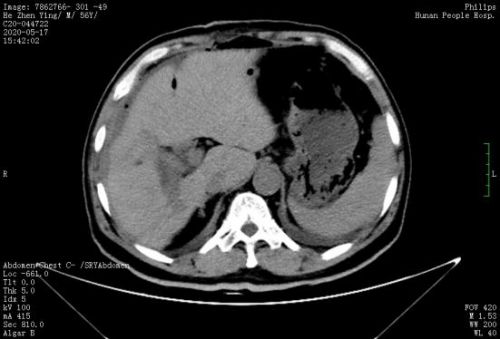

术前ct示肝内胆管结石。

河北57岁的王先生1年前因“上腹部疼痛不适”被诊断为“肝胆管结石”,在当地接受开腹胆道手术。近日,他因上腹部疼痛行CT检查发现,右后叶肝管及尾叶胆管长满铸型结石。由于结石位置刁钻难取尽,手术难度和风险大,被多家捷克论坛 婉拒手术。

术中情况如术前判断,腹腔内致密粘连,解剖结构难辨;肝方叶肥大增生,胆管狭窄亦为敞开肝门增加了很大难度。在胆道外二科专家团队的高超技艺和谨慎操作下,运用特色硬镜联合钬激光碎石方法,结合胆管高位切开及胆管微整形技术,在保肝的情况下清除肝内外胆管结石。手术历时3个小时顺利完成,术中无输血。术后复查肝内胆管结石全部取尽。

手术后,胆道外二科医护人员运用加速康复外科ERAS理念,采用多模式镇痛、早期鼓励患者开展机体功能锻炼等措施。术后第二天,患者即进流食,下床活动;术后第三天复查CT显示,肝内胆管结石已全部取尽,王先生向医护人员竖起大拇指连连称赞。(胆道外二科:胡霞红 米杨 )